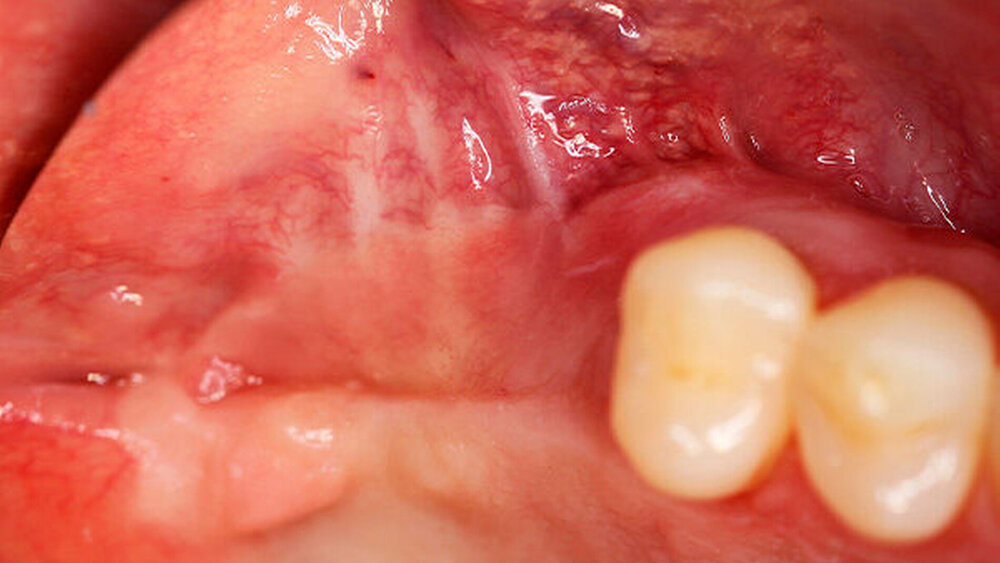

Ein 29-jähriger Patient stellte sich mit einer massiven Alveolarkammatrophie im rechten Unterkiefer in unserer Praxis vor. Diese lag in langen Jahren der Zahnlosigkeit begründet. Eine Beckenkammaugmentation kam für den Patienten nicht in Betracht. Dennoch wünschte er die Versorgung mit festsitzendem Zahnersatz. Nach ausführlicher Beratung entschied sich auch dieser Patient für eine Augmentation mit einem patientenindividualisierten allogenen CAD/CAM-gefertigten Knochenblock. Die DICOM-Daten des Unterkiefer-DVTs wurde an die Firma Zimmer gesendet, und es erfolgten wie im oben beschriebenen Fall eine virtuelle Planung und das virtuelle Design des allogenen Knochenblocks anhand der geplanten Implantatpositionen. Nach der üblichen Kontrolle und Freigabe des Chirurgen erfolgte die eigentliche Fertigung und Übersendung des Knochenblocks in die Praxis. Die Augmentation erfolgte auch in diesem Fall in Vollnarkose unter antibiotischer Abschirmung perioperativ mit Ampicillin. Die Schnittführung im Unterkiefer unterscheidet sich von der Sockelschnittführung im Oberkiefer aufgrund der Anatomie (N. mentalis). Auch bei diesem Patienten wurde eine tief im Vestibulum liegende bogenförmige Inzi‧sion durchgeführt, jedoch ohne die vertikalen Entlastungen. Nach streng subperiostaler Präparation erfolgte die Darstellung des N. mentalis. Die Vorbereitung des Spenderbetts sowie die Wässerung, Einpassung und Befestigung des allogenen Knochenblocks gestalteten sich wie im Fallbeispiel 1. Die Heilzeit des Knochenblocks dauerte ebenfalls sechs Monate. Zwei Implantate (Straumann) wurden nach krestaler Schnittführung in Lokalanästhesie eingebracht und heilten subgingival binnen drei Monaten ein. Aufgrund des massiven Volumenzuwachses war auch ebenfalls eine Vestibulumplastik im Zuge der Implantatfreilegung notwendig. Das Prozedere verlief ebenfalls wie im Fallbeispiel 1. Das freiliegende Gewebe wurde mit einer Kollagenmatrix abgedeckt. Dadurch konnte die Breite der befestigten Gingiva deutlich verbreitert werden.